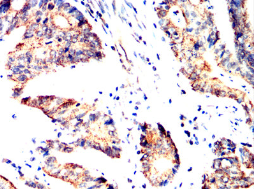

SH2B2 Mouse Monoclonal antibody[5E117]

AC3484 SH2B2 Mouse Monoclonal antibody[5E117] 100ug $367 10days

AC3484 SH2B2 Mouse Monoclonal antibody[5E117] 200ug $660.6 10days

Immunogen :   Purified recombinant fragment of human SH2B2 (AA: 497-676) expressed in E. Coli.

IHC    1/200 - 1/1000